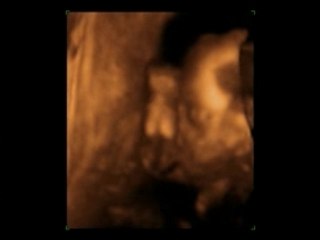

Echo morpho Caroline